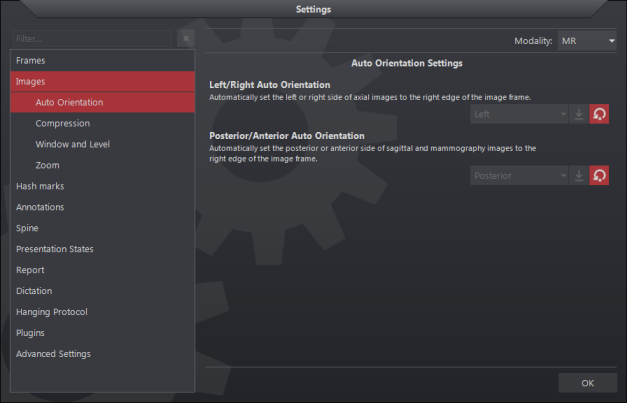

Automatikus orientáció engedélyezéséhez:

- Válassza ki az Eszközök/Opciók lehetőséget

- Kattintson a Képek fülre

- Az Automatikus orientáció részben jelölje be a jelölőnégyzetet a megfelelő pozíció konfigurálásához

- Az L/R az axiális képek bal (L) vagy a jobb (R) oldalát állítja be a képkocka jobb széléhez

- A P/A a szagittális és mammográfiás képek posterior (P) vagy anterior (A) oldalát a képkocka jobb szélére állítja.

- A beállítás mentéséhez nyomja meg az OK gombot